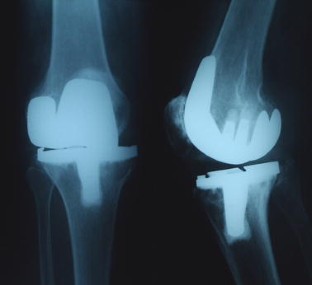

Multilobulated popliteal cyst after a failed total knee arthroplasty

Popliteal cyst is a rare finding after total knee arthroplasty (TKA), but when present, it might indicate a malfunction of the TKA related to generation of wear-particles, or loosening. We present a case of a multilobulated popliteal cyst developing in a patient 8 years after primary TKA. The cyst was associated with a mechanical prosthetic loosening. The primary complaint of the patient was pain in the posterior region of the knee. A two-stage procedure consisting of cyst excision at first, followed after 5 months by a revision TKA was performed. Intraoperatively, a darkish, multilobulated cyst with a well-defined thick wall filled with fluid containing polyethylene debris, communicating with the knee joint was found. After 3 years of follow-up, the patient was satisfied and walked without the support of a cane. The patient presented a satisfactory knee range of motion. Clinical, radiological and ultrasound investigations ruled out popliteal cyst recurrence. A dissecting popliteal cyst associated with a failed TKA should be excised because it contains polyethylene debris that constitutes an induced factor for prosthetic loosening. A two-stage procedure with quite a long time in-between, as presented in this paper, can be a useful alternative to manage such a problem, in particular in very old patients associated with other medical problems.

Fig. 1